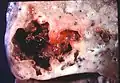

Pathology image of a lung abscess.

Lung abscess is a type of liquefactive necrosis of the lung tissue and formation of cavities (more than 2 cm)[1] containing necrotic debris or fluid caused by microbial infection.